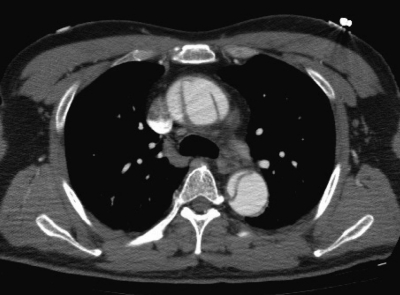

血液所見:白血球 21,000。血液生化学所見:AST 15 U/L、ALT 15 U/L、LD 261 U/L (基準 176〜353)、尿素窒素 18 mg/dL、クレアチニン0.6 mg/dL、尿酸 6.4 mg/dL、血糖 115 mg/dL、Na 142 mEq/L、K 3.8 mEq/L、Cl 107 mEq/L、心筋トロポニンT陰性。心電図に異常を 認めない。胸部造影CTを示す。